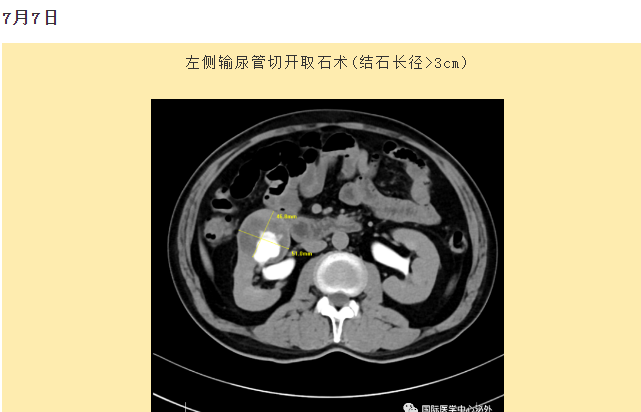

西安國際醫(yī)學(xué)中心醫(yī)院順利完成了達(dá)芬奇Xi(第四代)機(jī)器人裝機(jī)。7月6日—7月15日,泌尿外科成功完成了達(dá)芬奇Xi(第四代)機(jī)器人手術(shù)6例,標(biāo)志著科室微創(chuàng)外科邁入新時(shí)代,造福萬千患者。